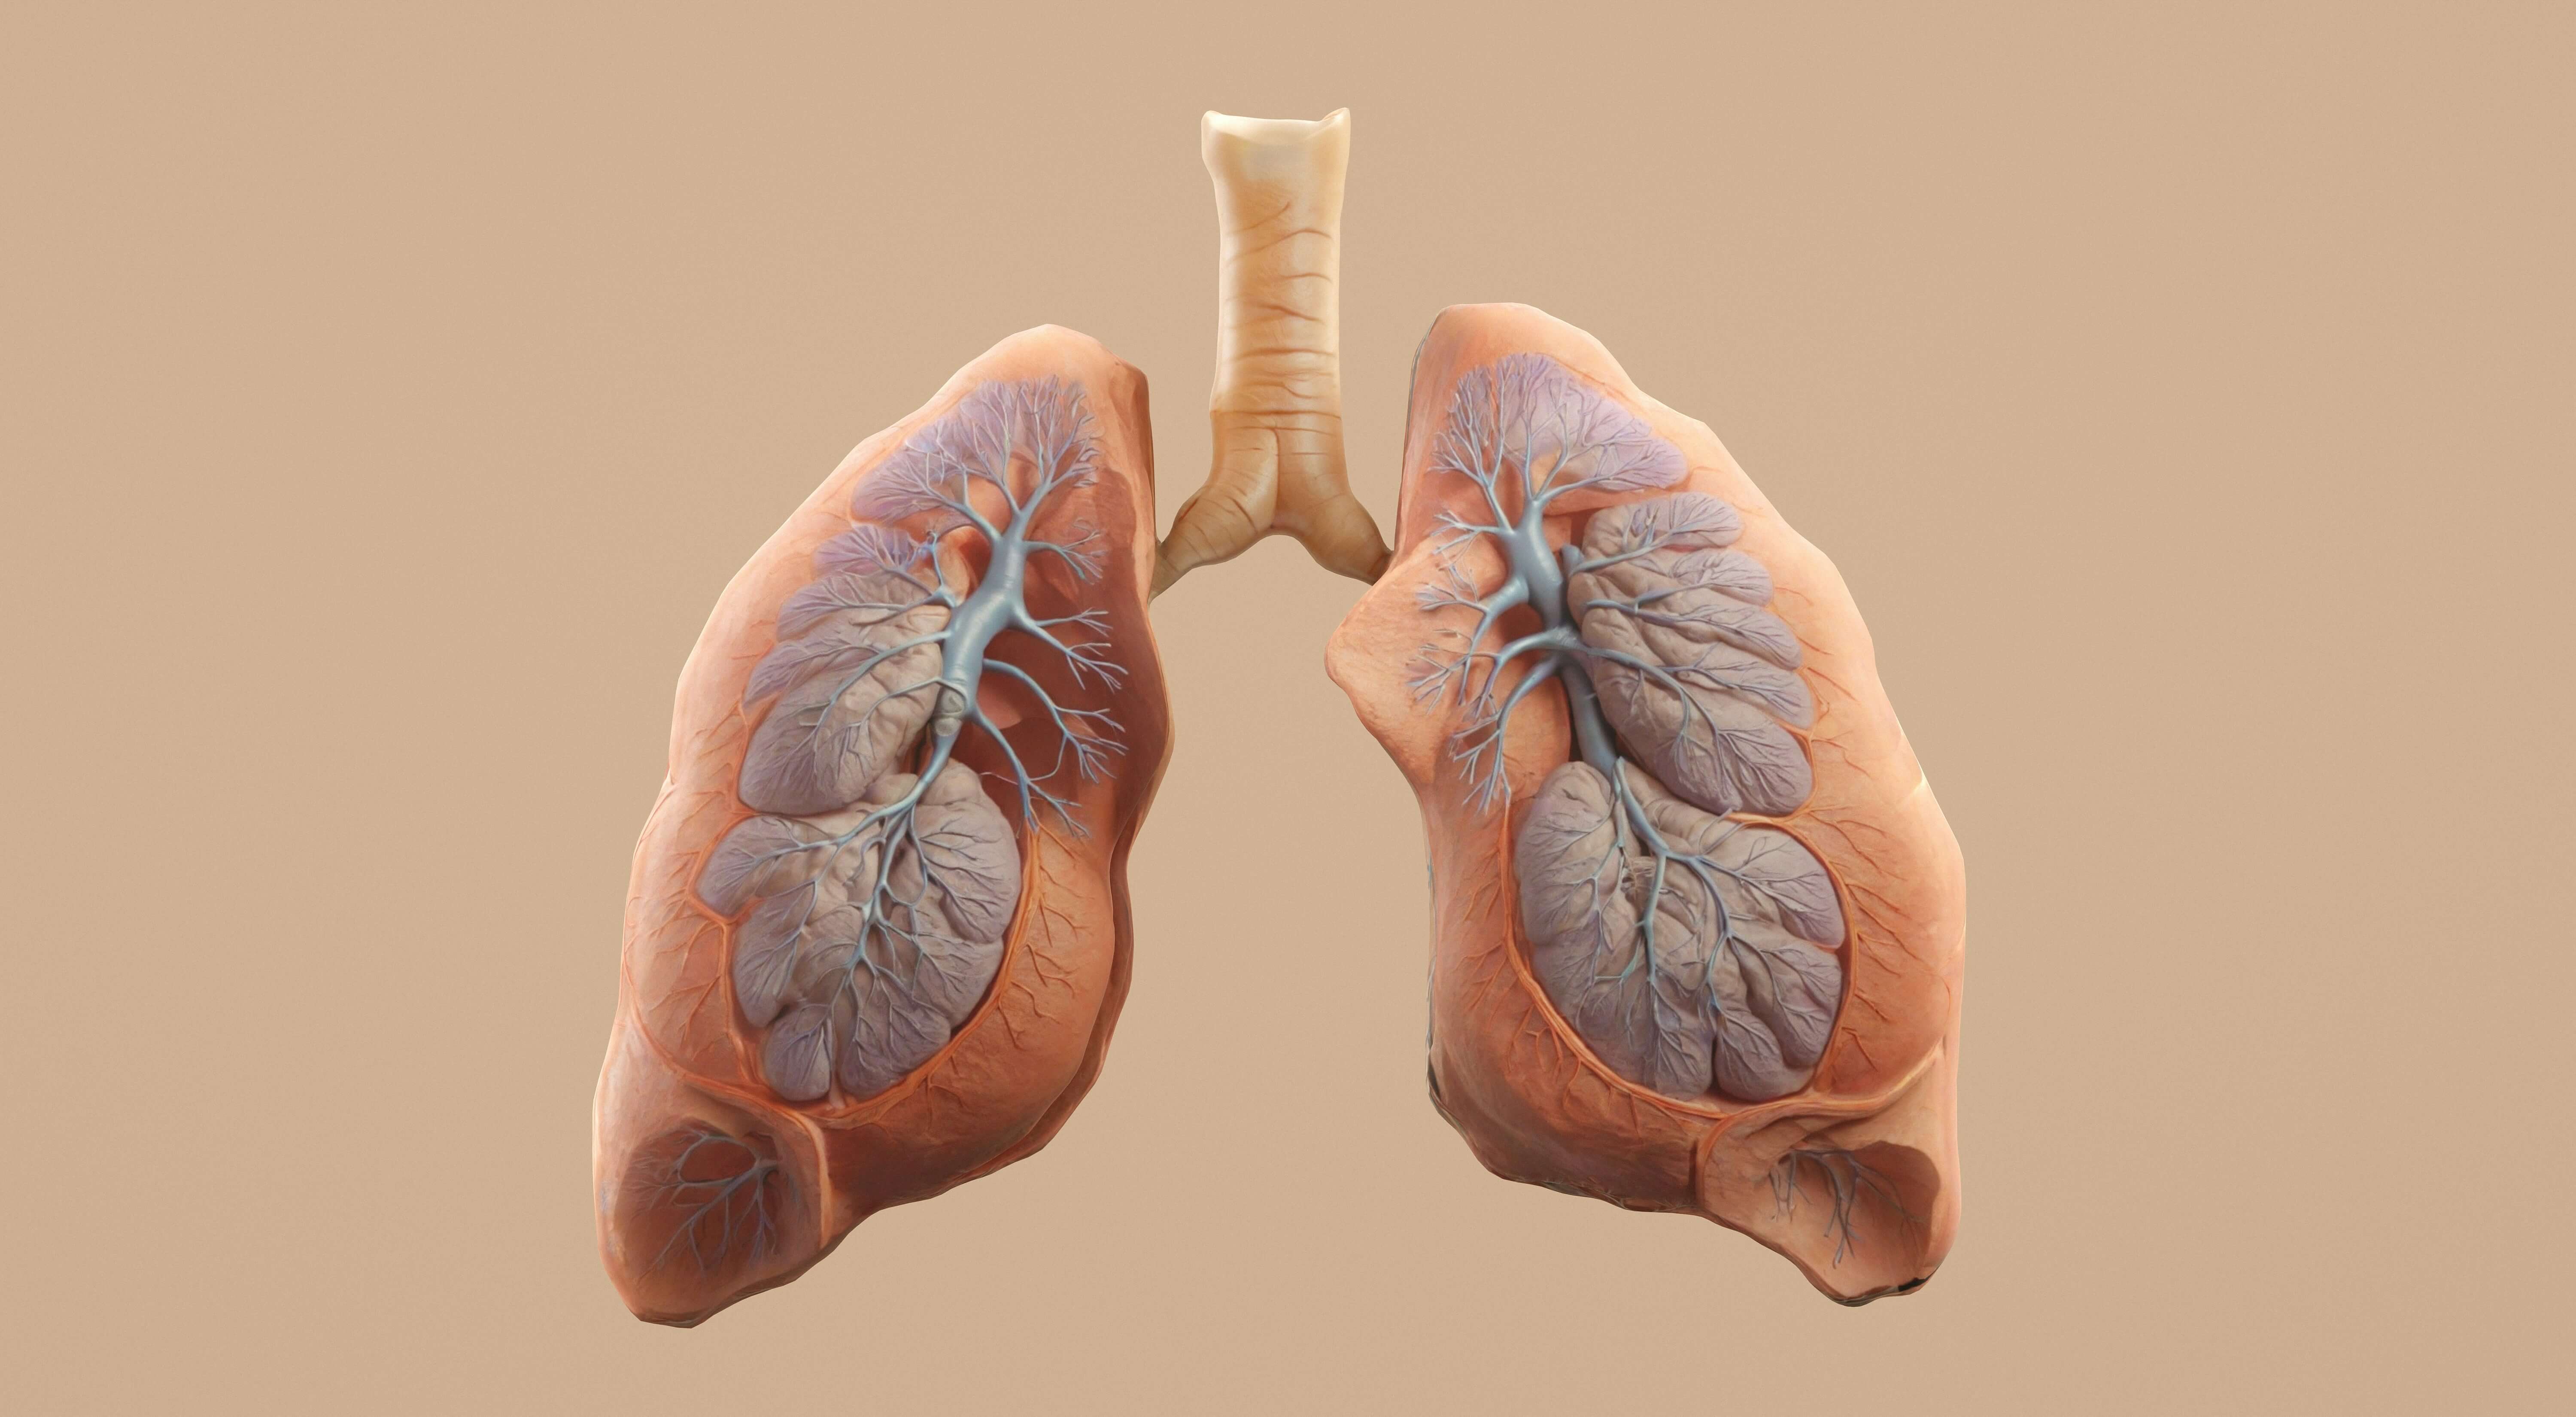

현대 사회에서 폐암은 조기 발견이 매우 어려운 질환으로 알려져 있습니다.

폐암, 왜 조기발견이 중요할까요?

폐암은 초기에는 특별한 증상이 나타나지 않는 경우가 많지만, 몸에서 보내는 미세한 신호들이 있습니다.